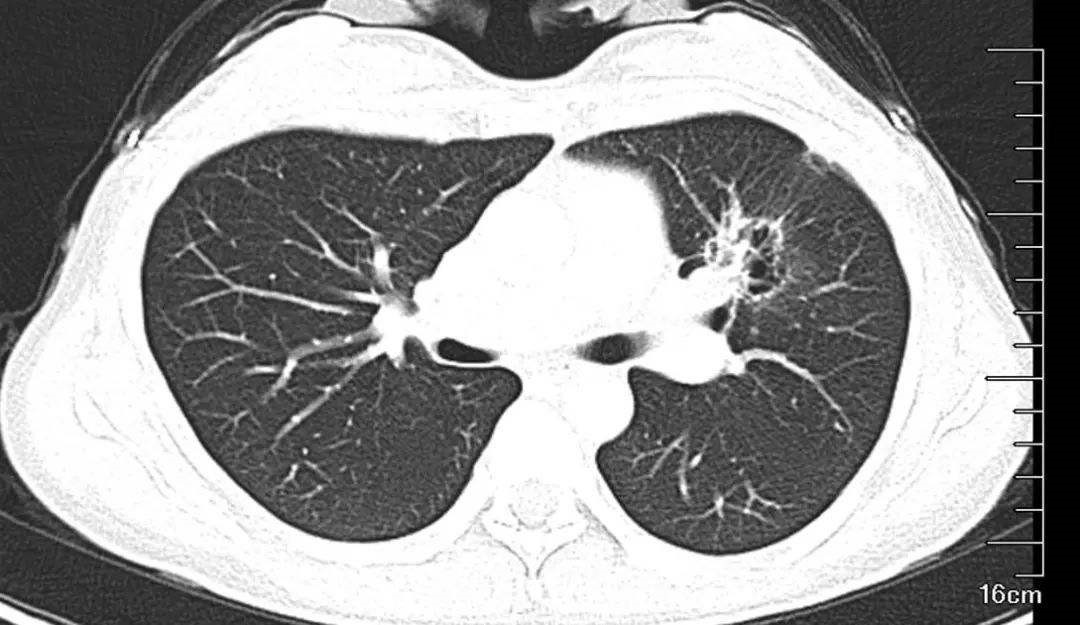

憋住气的效果